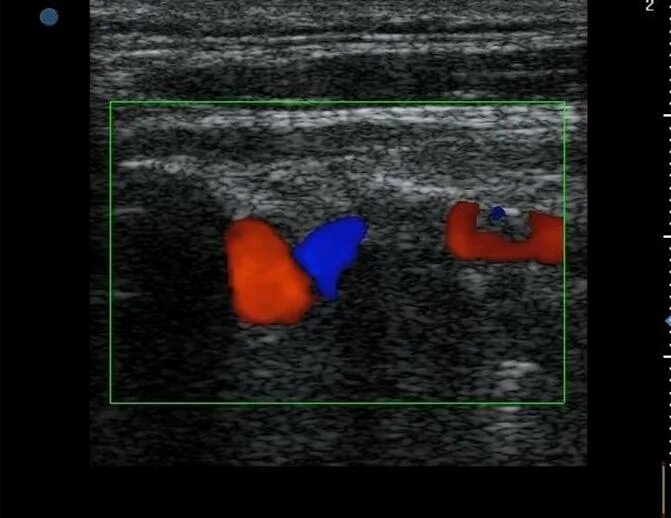

S образный изгиб артерии